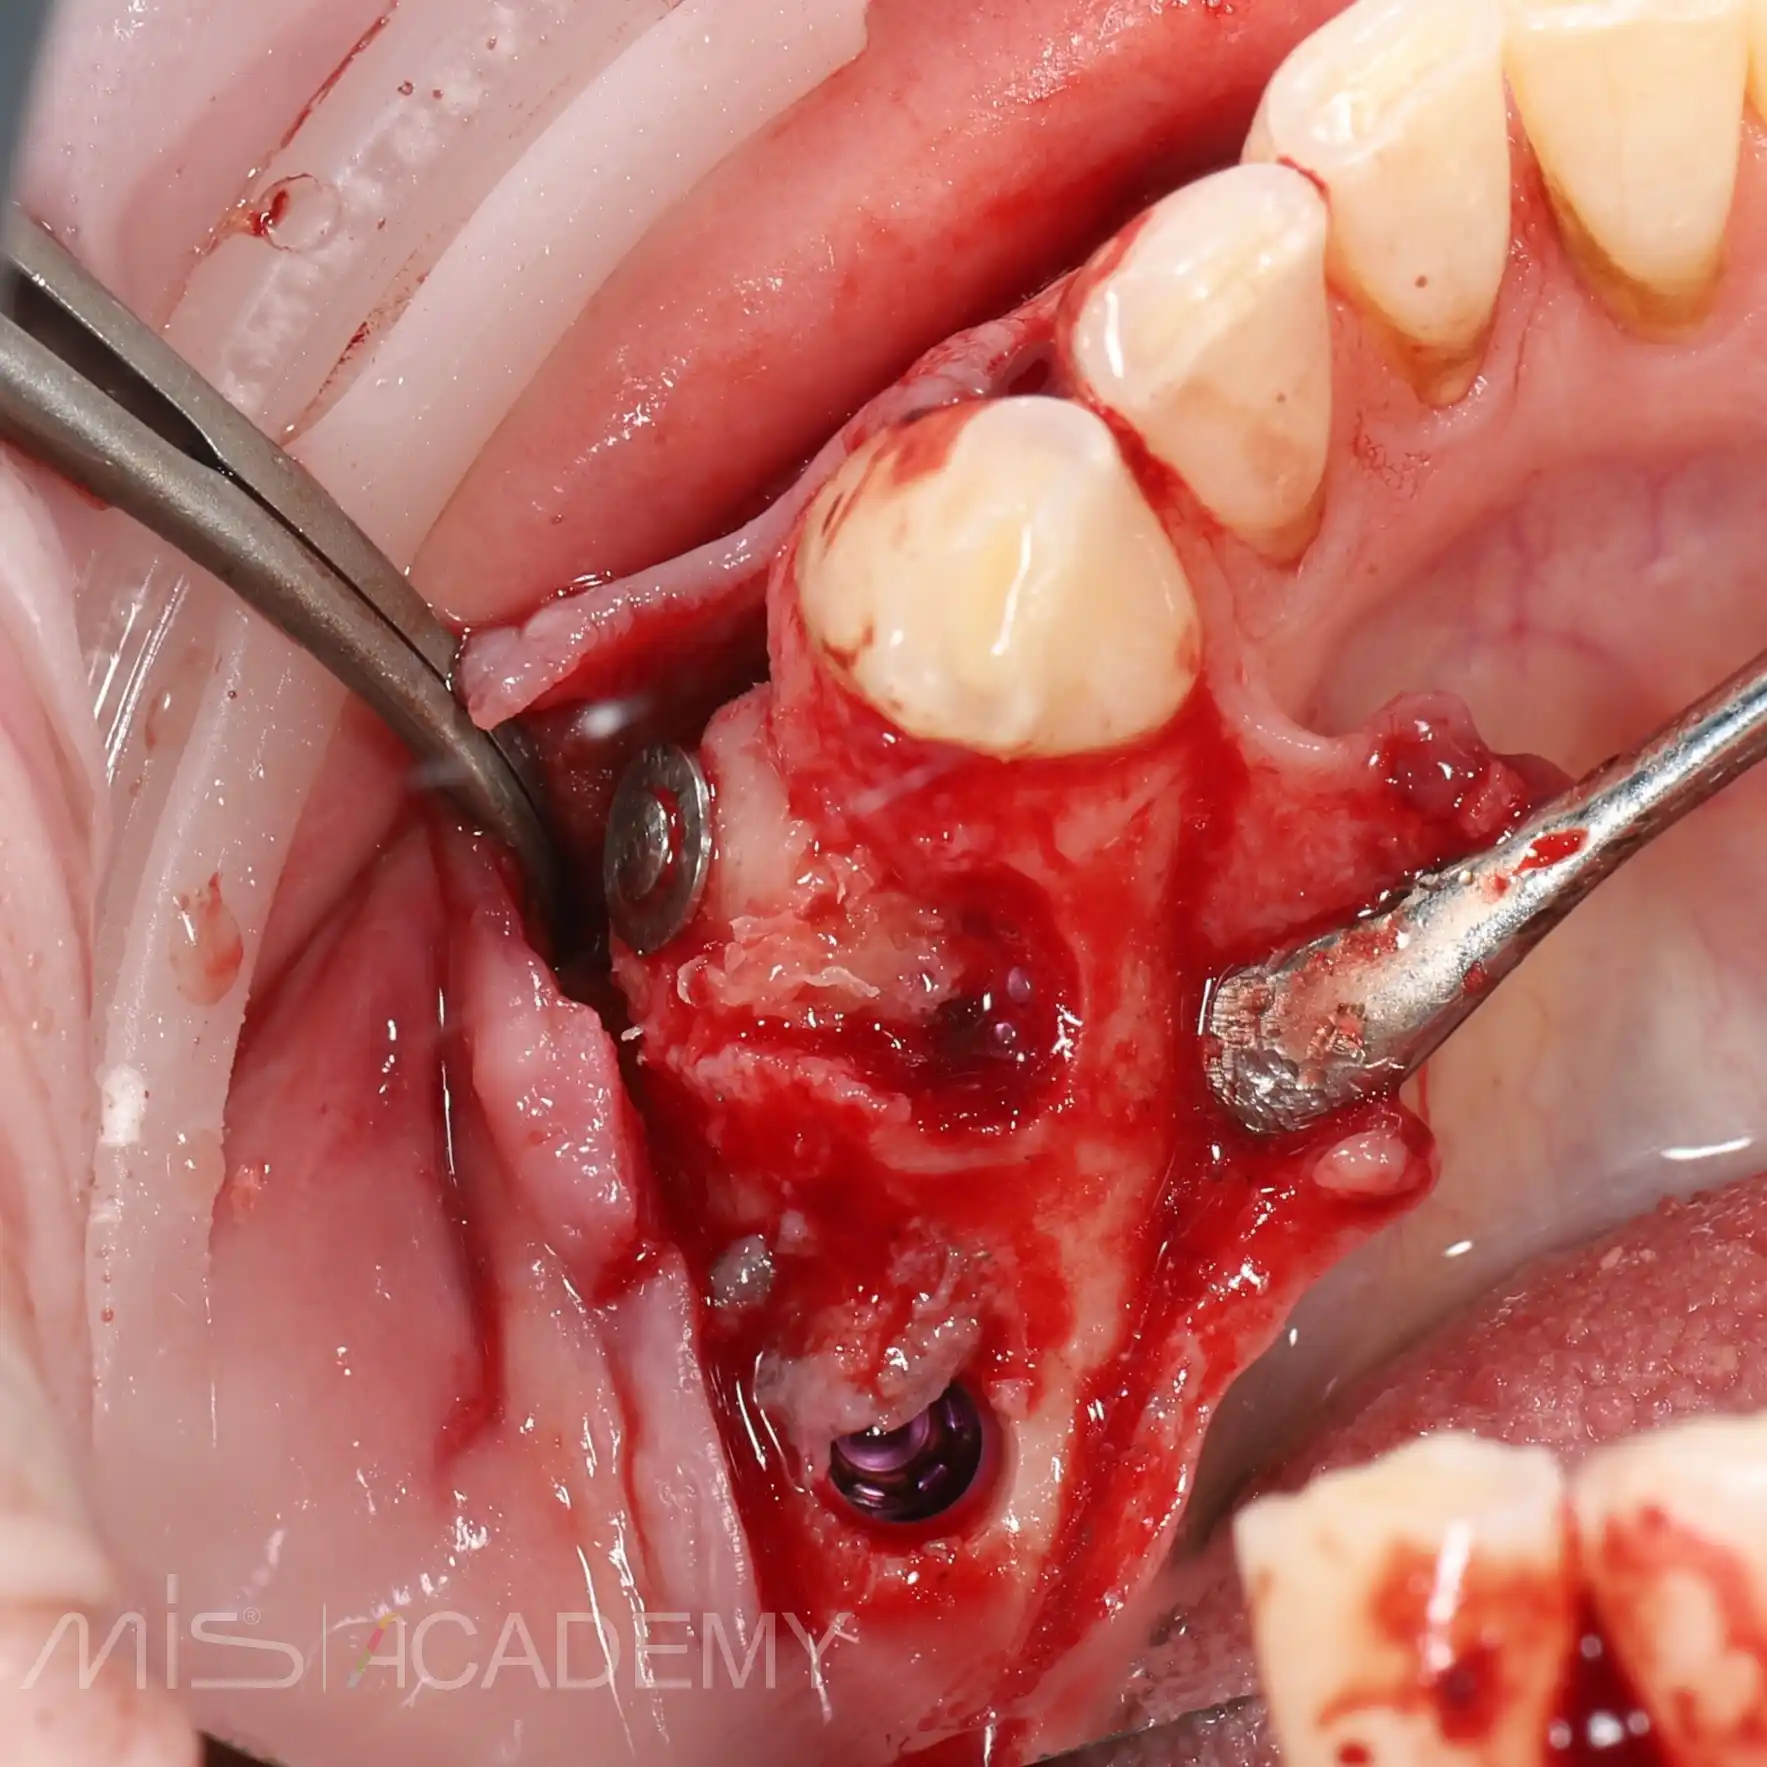

— На первом этапе был удален зуб 4.4 и установлены 2 имплантата Mis Implants C1 в области 4.4 и 4.6 (free-hand).

— Закрыли костный дефект с помощью блока из бугра ВЧ (B2S) и ССТ в области имплантатов 4.6 и 4.7.